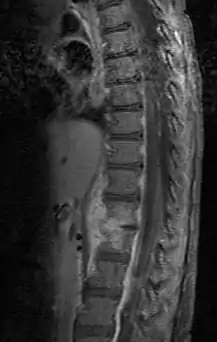

| Discitis in a 2 year old child. | |

Discitis, or diskitis, is an infection in the intervertebral disc space that affects different age groups. In adults, it can lead to severe consequences, such as sepsis or epidural abscess, but it can also spontaneously resolve, especially in children under 8 years of age. Discitis occurs post-surgically in approximately 1–2 percent of patients after spinal surgery.

Diagnosis is usually apparent on MRI although plain X-rays and CT examinations can be suggestive. The MRI will reveal air changes in the disc and possibly even external involvement involving the bone or epidural regions. A biopsy may be performed and helps with diagnosis in some cases but often an organism is not obtained. C-reactive protein levels and ESR levels will be elevated and are useful for treatment. Often, the white blood cell count will be normal and the patient will be afebrile.